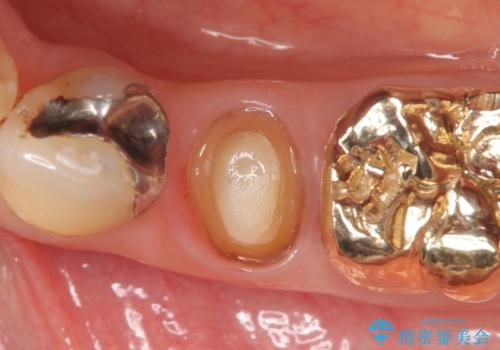

- 左下5番目の歯を根管治療からやり直したいといらっしゃった方の症例です。

再根管治療終了後、オールセラミッククラウンによる補綴を行いました。

今回用いたオールセラミッククラウンはジルコニアフレームという白い素材の上にセラミックを盛っているため、審美性が非常に高いのが特徴です。